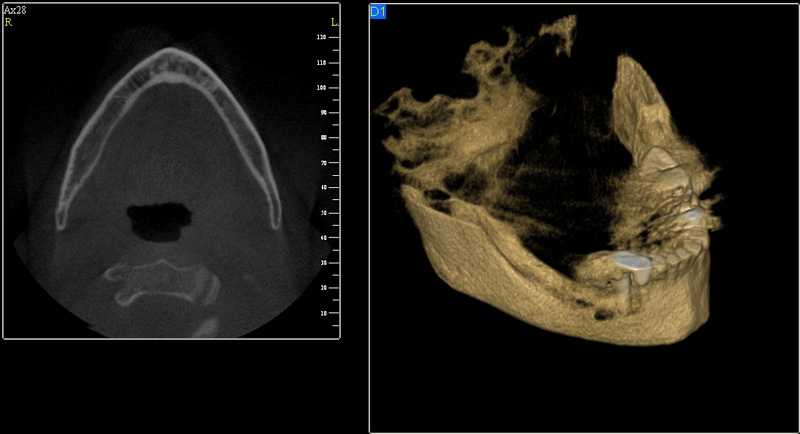

Tyto postupy nám umožní doplnit chybějící množství kosti v čelistech pacienta i zlepšit kvalitu kosti. Většinou se setkáváme s omezenou nabídkou kostní tkáně díky resorpčním (úbytkovým) procesům způsobených věkem či vytržením zubu, přítomností anatomických struktur jako je čelistní dutina, nervový kanál nebo patologických či poúrazových stavů - cysty, zlomeniny.

Nejčastější oblastí pro doplnění kosti je čeleni dutina horní čelisti.

Tento výkon se nazývá sinus lift - aplikace kostního granulátu do čelistní dutiny

Při ztrátě molárů a premolárů v horní čelisti a jejich náhradě implantáty se často setkáváme s nedostatečnou vertikální nabídkou kosti pod čelistní dutinou, často doprovázenou i nedostatečnou horizontální nabídkou a sníženou kvalitou kosti

(v oblasti 2. premoláru v 50%, v oblasti moláru až v 80% případů nedostatečná kostní nabídka)

Od roku 1985 je tento problém řešen augmentační operací nazývanou sinus lift.

Jedná se o vyzvednutí membrány, která čelistní dutinu vystýlá, pod vyzvednutou membránou vznikne kapsa, kam se umístí augmentační materiál, do kterého se zavedou implantáty.